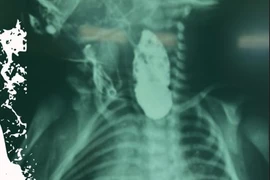

Bé sơ sinh bị suy hô hấp nặng hồi phục kỳ diệu

Trong quá trình điều trị, tình trạng của bé nhiều lần rơi vào nguy kịch do tổn thương phổi nghiêm trọng, rối loạn đông máu, tổn thương gan – thận.